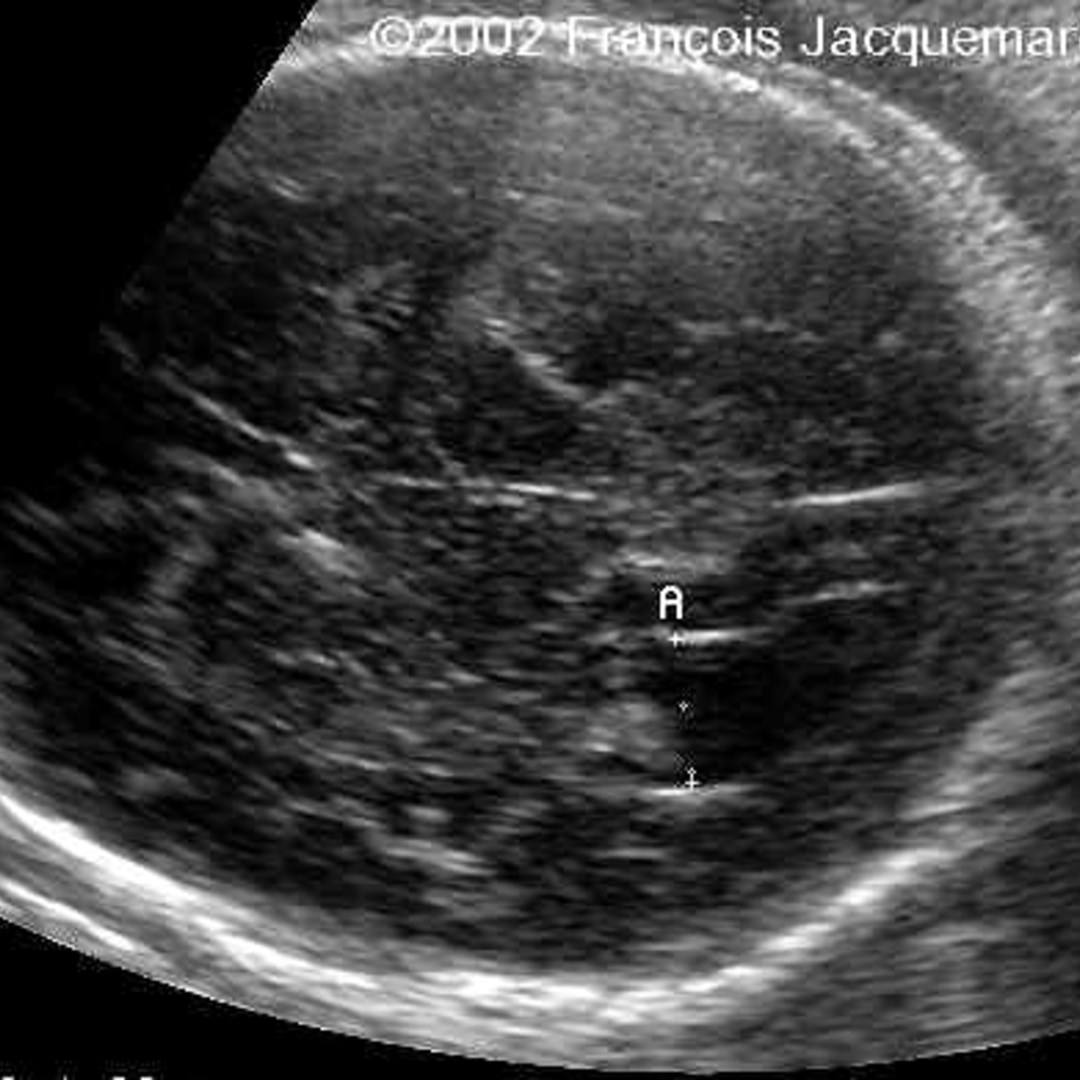

Lipoma of the spermatic cord. (a) US image demonstrates an echogenic …

Gastric lipoma

Gastric submucosal lipoma | Radiology Case | Radiopaedia.org

Gastric lipomas are a location-specific subtype of gastrointestinal …